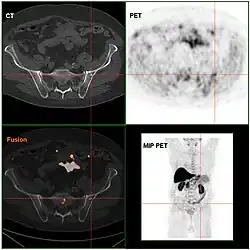

Pozytonową tomografię emisyjną (PET) wykorzystuje się w ocenie zaawansowania raka gruczołu krokowego[297].

PET ze znakowaną choliną (11C-cholina i 18F-cholina) wykazuje większą czułość i swoistość w ocenie obecności przerzutów do kości i do węzłów chłonnych niż scyntygrafia czy mpMRI[297]. W badaniu porównującym skuteczność PET ze znakowaną choliną ze scyntygrafią i tomografią komputerową brzucha wykazano wyższą czułość i swoistość PET ze znakowaną choliną w rozpoznawaniu przerzutów do kości niż scyntygrafii wynoszącą odpowiednio 100% i 86,4% dla PET oraz 90% i 77,2% dla scyntygrafii[298][297]. W innej metaanalizie czułość PET ze znakowaną choliną w wykrywaniu przerzutów do węzłów chłonnych została oceniona na 62%, a swoistość na 92%[299]. Ze względu na ograniczoną dostępność PET ze znakowaną choliną oraz niejasną efektywność kosztową rutynowymi metodami oceny obecności przerzutów w kościach pozostają scyntygrafia oraz tomografia komputerowa[297]. Metoda wykazuje umiarkowaną skuteczność w wykrywaniu przerzutów do węzłów chłonnych, dlatego nie jest zalecana w rutynowej ocenie rozsiewu do węzłów chłonnych[297].